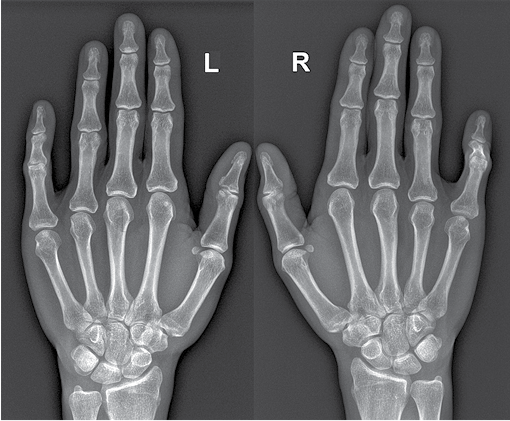

3 pav. Pacientės plaštakos (nugarinis paviršius)

4 pav. Pacientės plaštakos (matyti abiejų rankų penktųjų pirštų kontraktūra)

5 pav. Pacientės plaštakų rentgeno nuotrauka